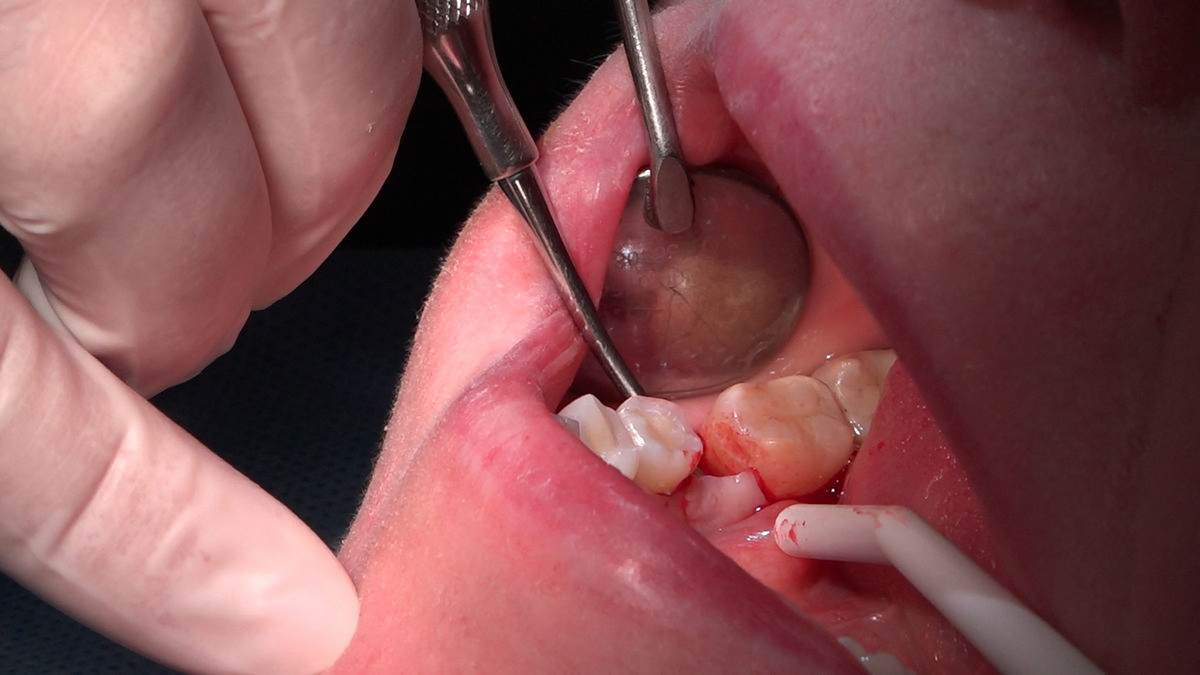

PRACTICULUM IMPLANTOLOGII - SEZON X - SESJA 4 - GRUPA B